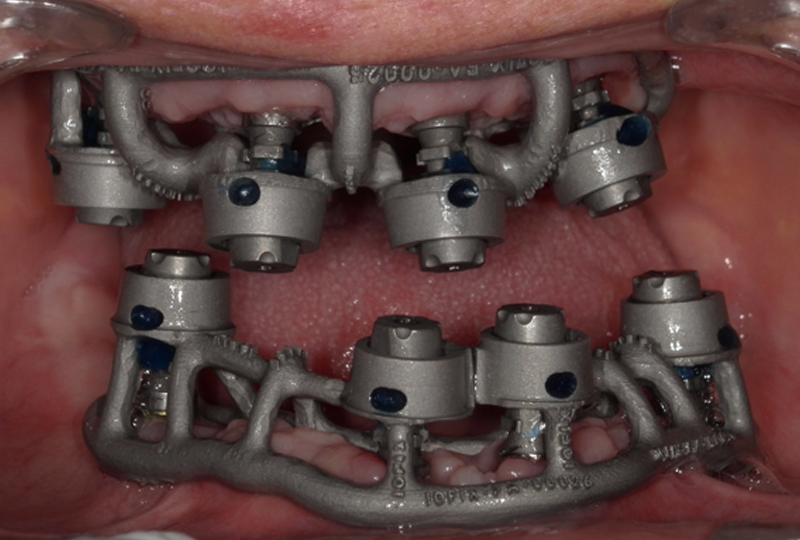

Durante la visita successiva a quella delle impronte (secondo appuntamento) veniva effettuata la prova estetica utilizzando dei prototipi delle protesi definitive. Infatti i progetti venivano stampati in 3D in resina (Dental-try®, Asiga) e provati per verifiche di congruità e approvazione del paziente (Figura 14). In questa stessa fase si validavano le mesh per ottenere delle basi di lavoro virtuali corrette. Il Ringfix® era collocato in bocca e fissato mediante resina fotopolimerizzabile a dei particolari scanbody chiamati Scantransfer (Scantransfer®, IPD) (Figura 15).

Gli Scantransfer prima del loro impiego sono misurati utilizzando un micrometro. L’azienda produttrice dichiara che la loro lunghezza è di 12,500 mm. In realtà dalle misurazioni effettuate si trovano discrepanze fino a +/- 9 micron. Anche queste differenze sull’asse Z sono corrette dall’avanzato algoritmo su cui si basa la sistematica IOSFIX®. L’insieme Ringfix®-Scantransfer® viene scandito di nuovo e analizzato (Figure 16,17).